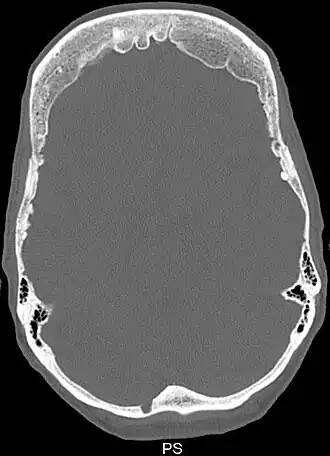

Снимок компьютерной томографии черепа пациента с гиперостозом лобной кости | |

Синдром Морганьи — Стюарта — Мореля (метаболическая краниопатия) — состояние, связанное с широким спектром эндокринных проблем, включая сахарный и несахарный диабеты и гиперпаратиреоз[1]. Другие признаки и симптомы включают головную боль, головокружение, избыточное оволосение по мужскому типу, проблемы с менструацией, галакторею, ожирение, депрессию и эпилептические припадки[1][2]. Утолщение внутренней поверхности лобной части черепа является, как правило, начальной стадией заболевания, известного как hyperostosis frontalis interna[1][3].

Диагноз ставят на основе жалоб и клинической картины; также используют гистологические методы исследования. На рентгенограмме визуализируется утолщение лобной кости. Синдром Морганьи — Стюарта — Мореля дифференцируют в первую очередь от болезни Иценко — Кушинга и адипозогенитальной дистрофии.